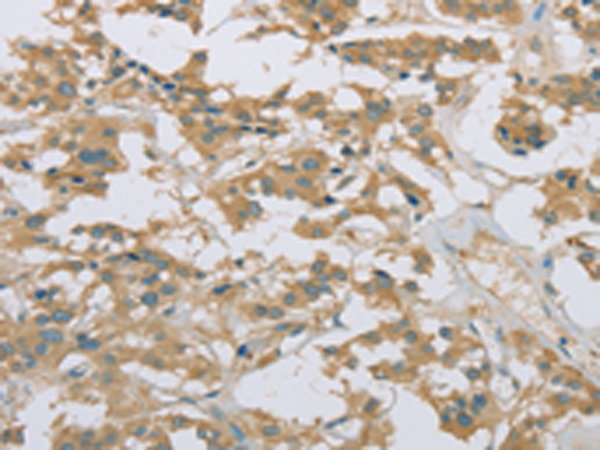

分类: 科研抗体货号: P08265别名: DEL1应用: WB,IHC反应种属: Human, Mouse